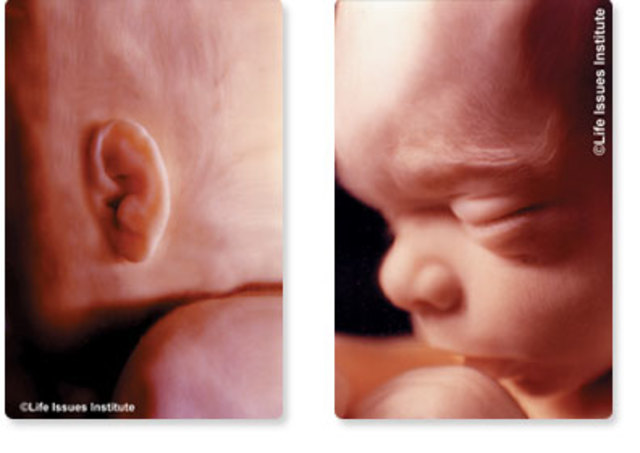

Los rasgos faciales se van modelando cada vez más. Los ojos, que al principio están muy separados entre sí, se van juntando hacia el centro de la cara. Las orejas ya no se sitúan tan bajas.

Los genitales externos tienen una morfología distinguible incluso fuera del útero.

El cuello empieza a elongarse y eso hace que las orejas se desplacen hacia arriba.

La cabeza sigue estando flexionada, de tal forma que la barbilla está constantemente tocando el pecho. Aparecen los labios en la boca. Los ojos siguen cerrados.

Los ojos siguen separados aunque cada vez se acercan más a la raíz nasal. En las orejas se distinguen los distintos pliegues que las componen. La barbilla se empieza despegar del tórax.

Todo su cuerpo, incluida su cabeza, está recubierto de ese pelo tan fino, el lanugo, pero su apariencia se humaniza en esta fase de su desarrollo. Las primeras zonas en las que el bebé empieza a tener pelo son las cejas y sobre el labio superior. Tras el nacimiento, este pelo se cae y empieza a crecer otro más grueso que nace de nuevos folículos pilosos. También se forman las uñas de las manos y de los pies del bebé: se diferencian de los dedos. Las manos se abren y cierran,